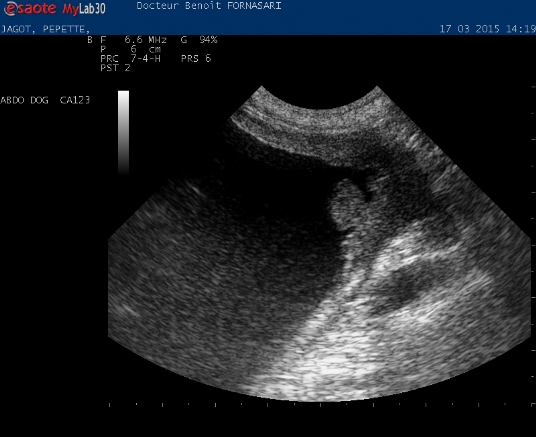

Mercredi 12 Septembre 2018 Animaux de compagniePhoto 1 La présence d'une masse pédiculée localisée au trigone vésical est fortement évocatrice d'une tumeur et en particulier d'un carcinome transitionnel.

Un carcinome vésical transitionnel est diagnostiqué chez une chienne beagle présentée pour hématurie en fin de miction et dysurie. Le traitement de ce cancer a pour objectif de diminuer la taille de la tumeur pour empêcher l'obstruction progressive des vo...